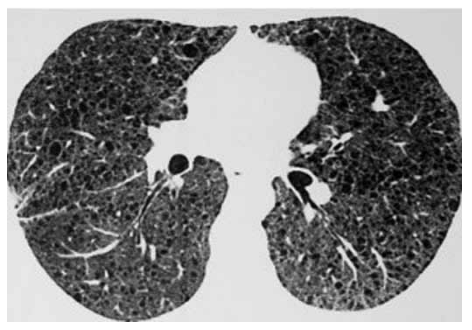

Paciente feminina, 38 anos, tabagista 2 anos/maço (esporádica), apresenta dispneia progressiva e já foi submetida a

dois procedimentos de drenagem pleural direita nos últimos

dois anos. Antecedentes pessoais: tumor muscular operado há 20 anos, sem diagnóstico histológico disponível no

momento. Ultrassonografia abdominal: nódulos renais.

Tomografia de tórax atual a seguir:

Biópsia pulmonar videoassistida revelou alargamento dos espaços alveolares, cistos pulmonares, pequenos nódulos periarteriolares e perialveolares as custas de proliferação de musculatura lisa. Positividade para o anticorpo monoclonal HMB-45 e para a pesquisa de alfa-actina de músculo liso (a-SMA).